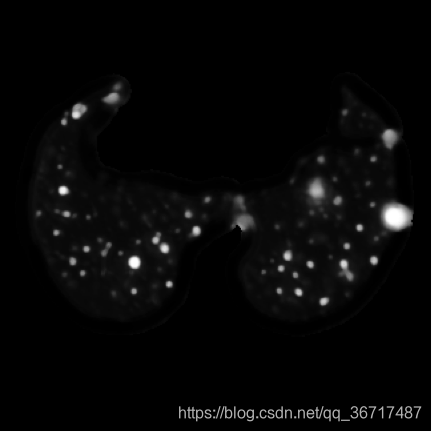

利用肺部分割生成的肺部区域图像,加上结节标注信息生成的结节mask图像,训练基于卷积神经网络的肺结节分割器。下图基于卷积网络的肺结节分割结果,对分割结果图像进行二值化,提取连通块等处理,提取出疑似肺结节。由于CT图像是一个扫描序列,参赛者可能需要对多帧的结果进行融合。